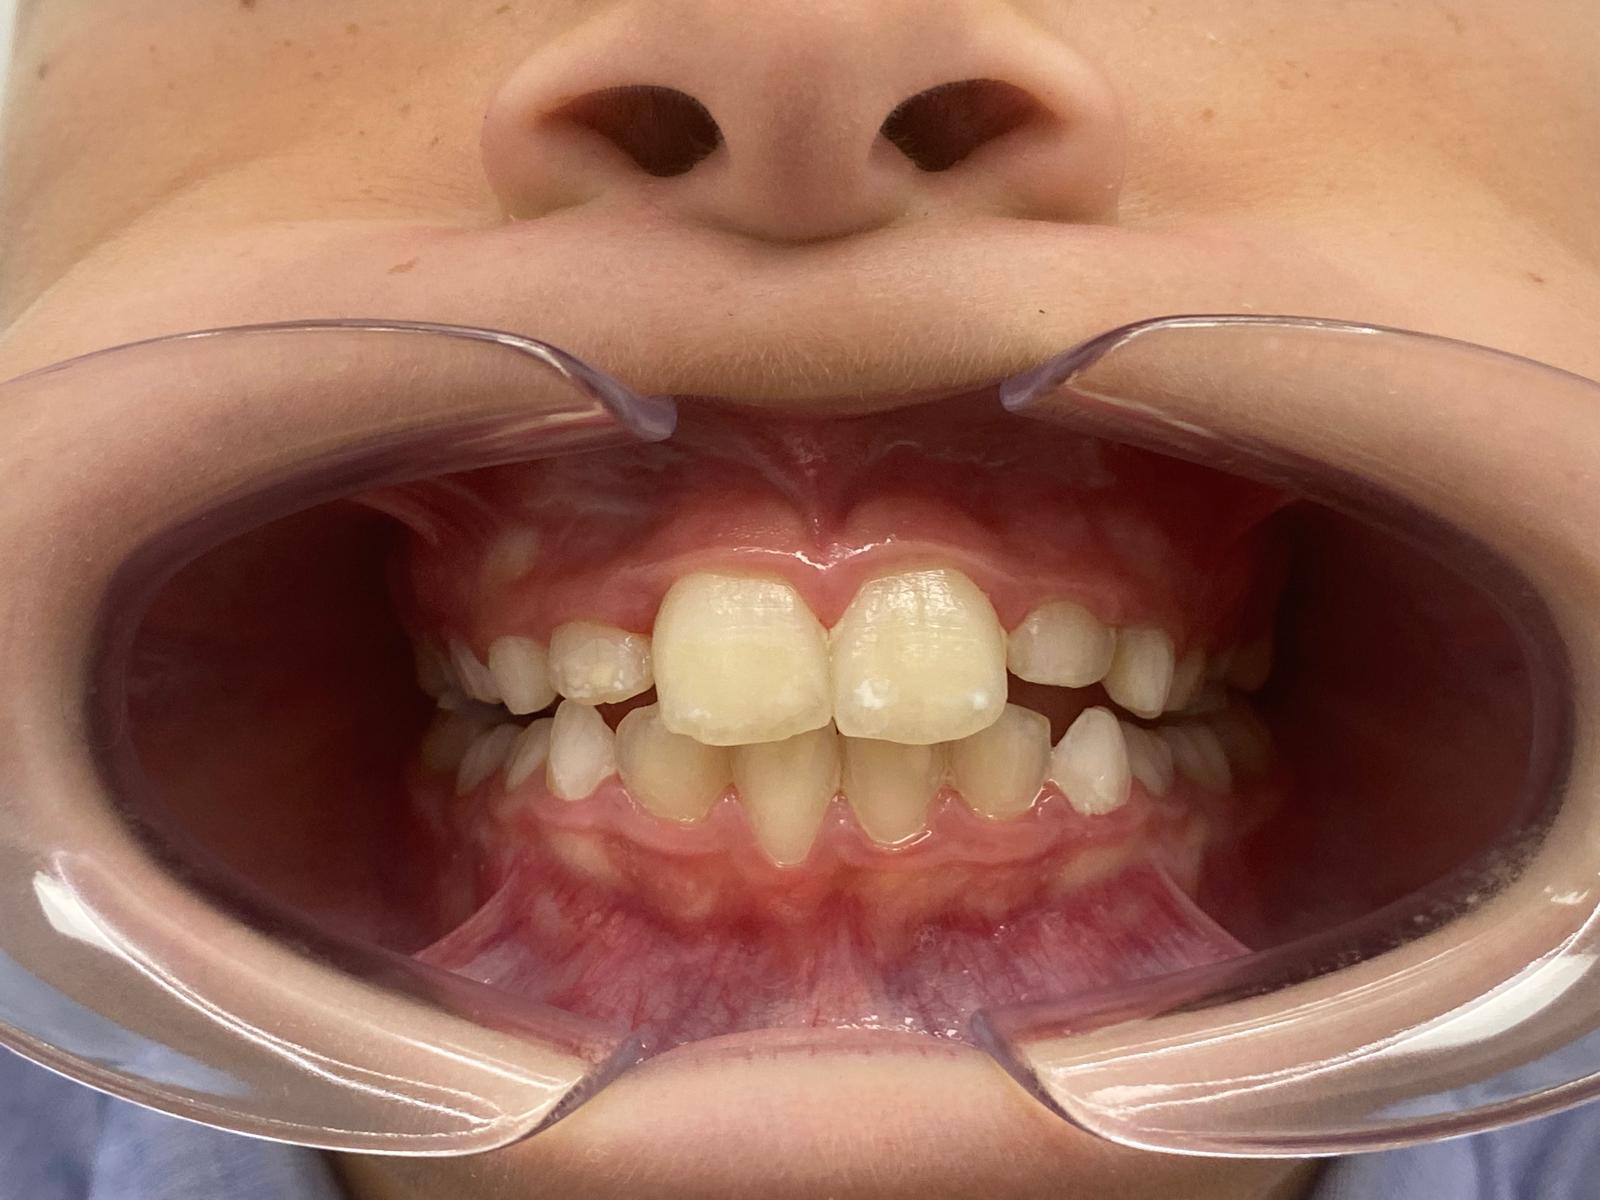

Intervención temprana en crecimiento para corregir mordida y desarrollo óseo

Martín acudió a consulta en fase de crecimiento con una alteración en la mordida anterior.

Los incisivos estaban bloqueando el desarrollo normal de los maxilares, lo que impedía que el crecimiento óseo siguiera su curso natural. Si no se intervenía a tiempo, este problema podía derivar en alteraciones más complejas en el futuro.

Tras realizar el estudio clínico y el análisis digital, se confirmó:

— Mordida cruzada anterior

— Bloqueo del crecimiento maxilar

— Falta de espacio para la correcta alineación dental

— Alteración funcional asociada a la respiración

Nos encontrábamos ante un caso en el que el momento de intervención era clave.

Tras el tratamiento, conseguimos:

— Corrección de la mordida anterior

— Desarrollo adecuado de los maxilares

— Espacio suficiente para la alineación dental

— Mejora de la función respiratoria

El resultado no solo es estético, sino también funcional y estable a largo plazo.